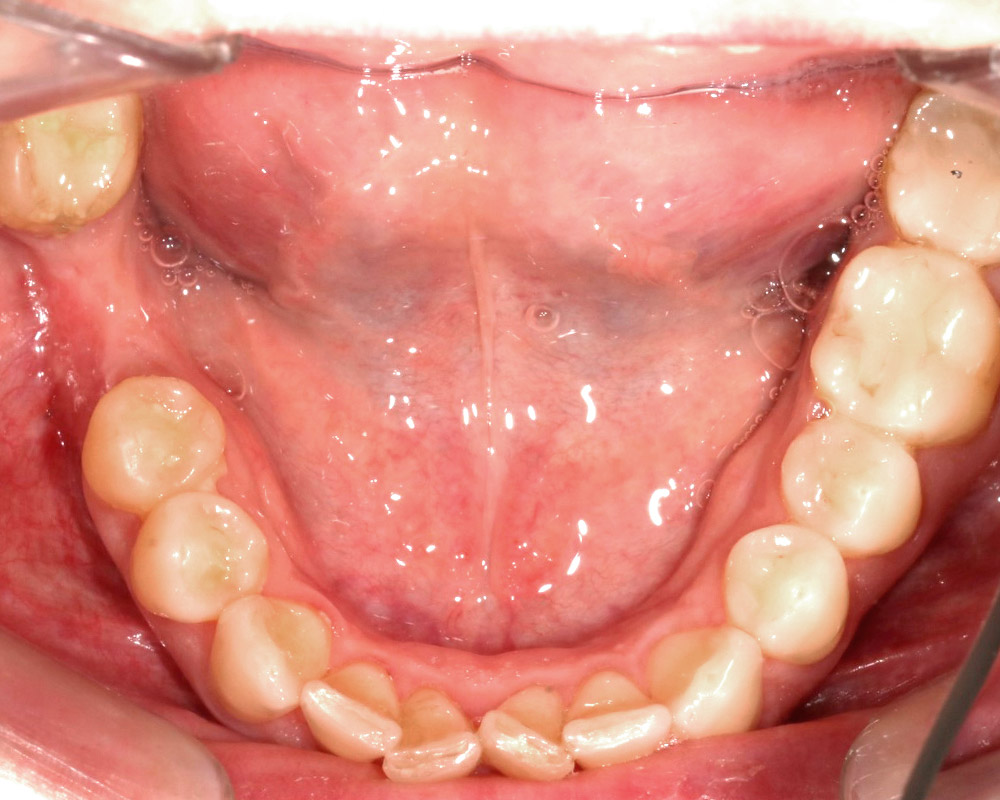

Кейс 21

Количество кап ВЧ 32

Количество кап НЧ 32

ДО

ПОСЛЕ